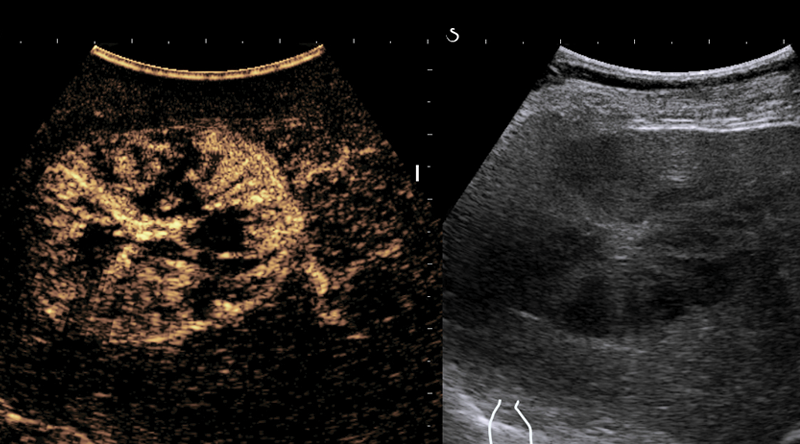

BRTO (Balloon occluded retrograde transvenous obliteration)

Bei Patienten mit behandlungsbedürftigen Ösophagus-, Magen-, oder ektopen Varizen bei denen ein TIPS nicht möglich oder nicht indiziert ist, kann die BRTO als Alternative zur endoskopischen Therapie erwogen werden. Zudem kann diese Methode auch zur Behandlung der refraktären Hepatischen Encephalopathie eingesetzt werden.